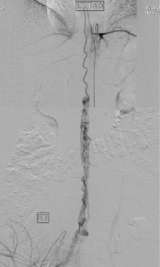

On the other hand, most dural or epidural AVFs are curable by surgery or catheter embolization. Our experience clearly shows “the sooner the treatment the better the outcome”. In our institution, minimally invasive catheter embolization was feasible in 75% of dural AVF cases. In the rest of 25% cases, surgical resection was performed. Both treatment methodologies result in a very high cure rate.

Figure 4: Catheter Embolization of a Spinal Dural AVF.

A microcatheter was navigated into a spinal dural AVF.

From the microcatheter, glue was injected into the AVF. After this, the lesion disappeared completely.